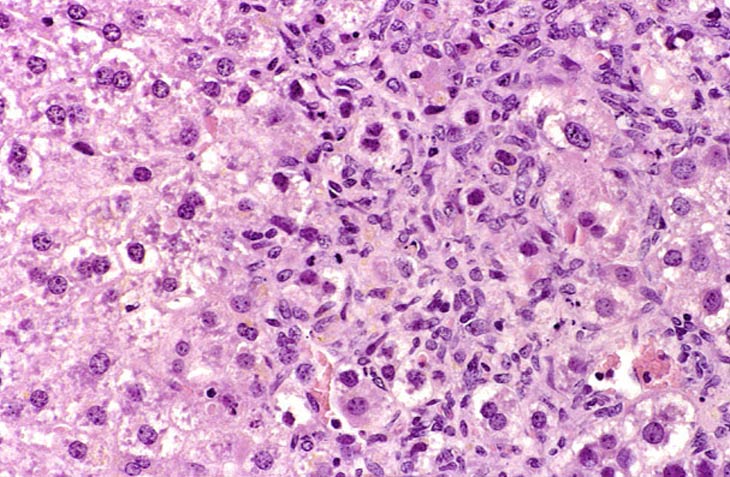

This change was originally diagnosed as endothelial cell proliferation. Based on the H&E stained sections, it is not possible to definitively identify the proliferating sinusoidal lining cells as endothelial cells but some have cytomorphological features consistent with endothelial cells. Low and high magnifications of endothelial cell hyperplasia.